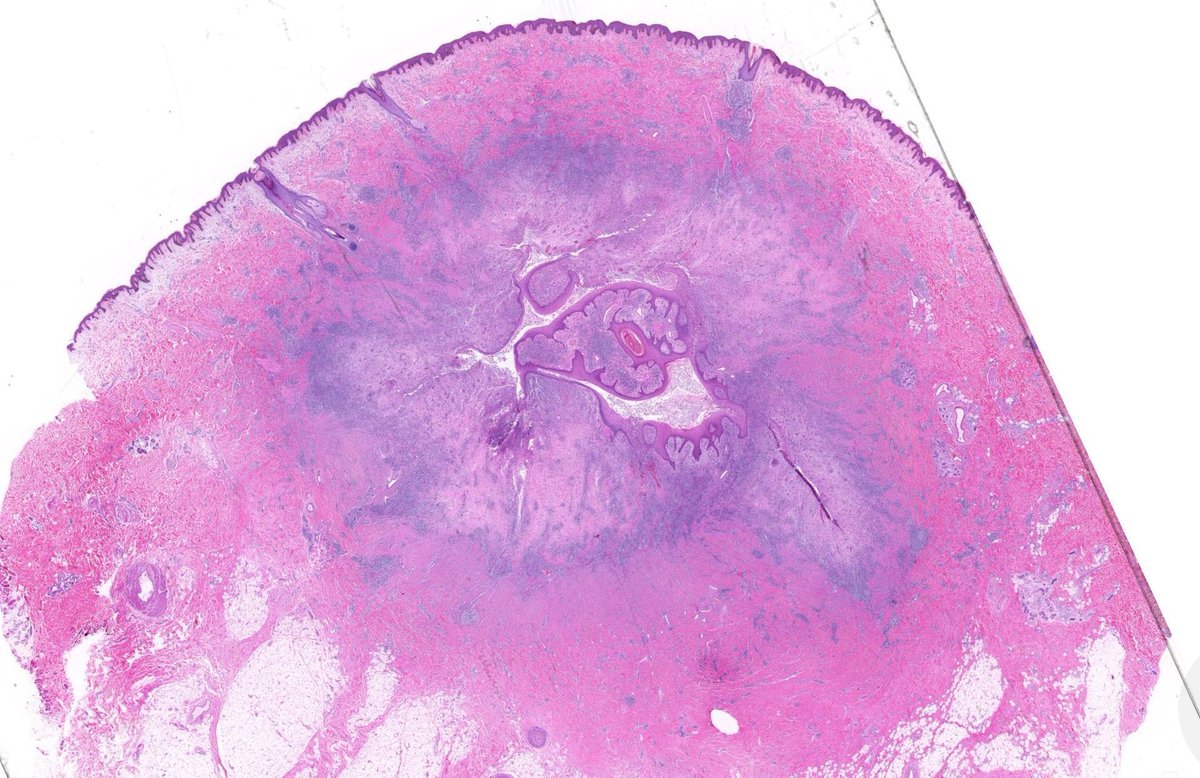

75 yo M. Big dorsal hand SCC with BONE invasion & multiple lymph node metastases. Why is this SCC acting so aggressively?!? Answer ✅ https://t.co/nVA7OgXMzh Digital slides: https://t.co/AMhtDEQjqA

#pathology #pathologists #pathTwitter #dermpath #dermatology #dermtwitter